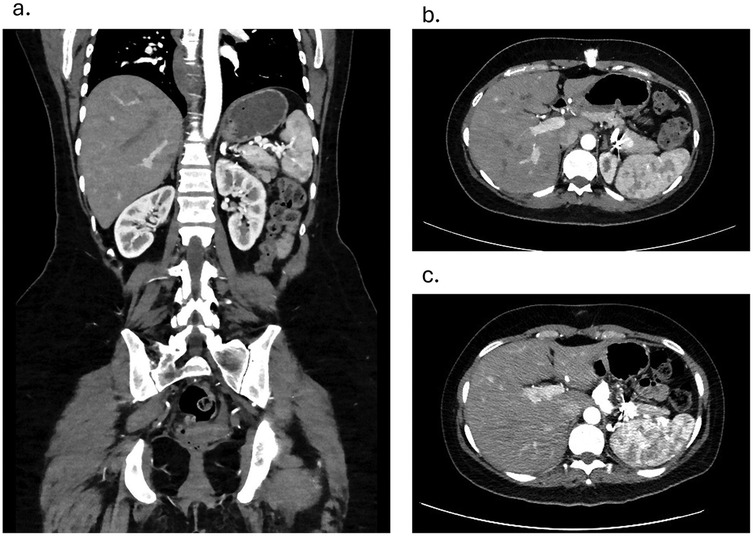

Follow-up after 3 and 6 months on CT angiography revealed that the stent was in an adequate position with no hematoma or contrast leakage (Figures 3a–c). Thrombosis of the aneurysm sac was confirmed as the excluded sac was not visualized and likely has resolved. The spleen was well-perfused and normal in size, and no infarction was noted. No reintervention was needed or performed, and no enlargement of the distal SAA was seen. The patient remained asymptomatic throughout. Prenatal evaluation 10 months later revealed no issues preventing pregnancy, and the patient became pregnant a year after the procedure, delivering at 34 weeks without long-term complications. The child remains healthy with normal growth. Throughout pregnancy the patient received routine prenatal care, and no additional imaging was performed to assess the repair site. During pregnancy, the patient remained on the same dual antiplatelet therapy with unchanged dosage and frequency; however, it was discontinued at 12 weeks due to bleeding, and then resumed postpartum at the same regimen. From the patient's perspective, she was reassured by the minimally invasive treatment that preserved her fertility and enabled a safe pregnancy and healthy child.

Figure 3. (a) coronal view contrast enhanced CT angiography showing patent stent and a well-perfused spleen on 3 months follow-up. (b) Axial view Contrast Enhanced CT angiography showing coiled branches and a well-perfused spleen on 3 months follow-up c. Axial view Contrast Enhanced CT angiography showing coiled branches and a well-perfused spleen on 6 months follow-up.